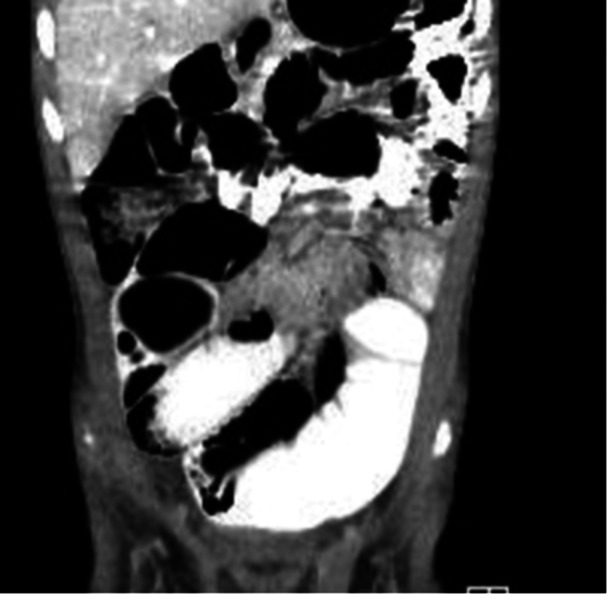

Pediatric intestinal pseudo-obstruction (PIPO) is a rare and severe disorder of gastrointestinal (GI) motility; patients with PIPO display signs and symptoms of intestinal obstruction in the absence of occluding lesions. Chronic atrial and intestinal dysrhythmia (CAID) syndrome is an exceedingly rare autosomal recessive disorder caused by mutations in the SGO1 gene; SGO1 mutations disrupt the cohesin complex, a protein involved in chromosome organization during cell division and hence, DNA stability. CAID leads to both GI and cardiac dysfunction. This case report highlights an exceptional instance of early-onset pediatric CAID marked by recurrent pseudo-obstruction and, notably, developmental delay, which has not been previously described. The case emphasizes the importance of genetic evaluation in pediatric patients with unexplained pseudo-obstruction, and the importance of multidisciplinary management.

Abstract Image